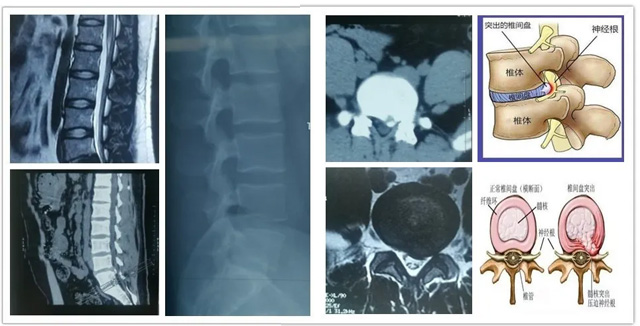

回想徐某來院的時候,那真是面帶痛苦,苦不堪言。他自稱“腰部劇痛2月余,厲害的時候無法站立”,這次是腰疼加重伴左下肢放射性疼痛一周,需要入院治療。查體發(fā)現(xiàn):腰椎生理曲度變直,腰4/5棘突及左側(cè)椎旁壓痛,左下肢放射痛,左直腿抬高試驗(yàn)30°(+)加強(qiáng)試驗(yàn)(+),仰臥挺腹試驗(yàn)(+),左足拇背伸、腓骨長短肌肌力較右側(cè)減弱,左側(cè)小腿外側(cè)、足背感覺減退。腰椎MRI提示:腰4/5椎間盤向左后方突出明顯。診斷:腰椎間盤突出伴坐骨神經(jīng)痛(L4/5)。

術(shù)前影像學(xué)資料

椎間孔鏡在內(nèi)窺鏡直視下可以清楚的看到突出的髓核、神經(jīng)根、硬膜囊和增生的骨組織。然后使用各類抓鉗摘除突出組織、鏡下去除骨質(zhì)、射頻電極修復(fù)破損纖維環(huán)。手術(shù)創(chuàng)傷小,皮膚切口僅7mm,出血不到20ml,術(shù)后僅縫1針,是同類手術(shù)中對病人創(chuàng)傷最小、效果最好的椎間盤突出微創(chuàng)療法,其臨床優(yōu)勢明顯。